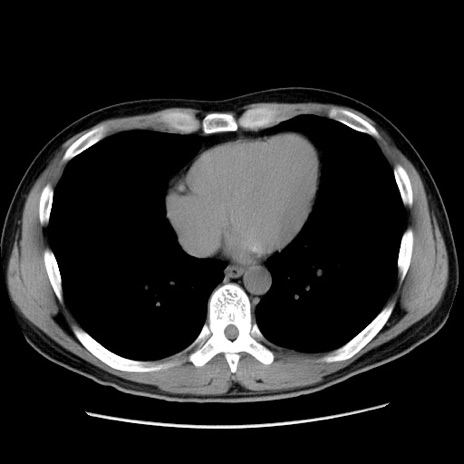

冠状断像

【症例】20歳代 男性

【主訴】心窩部痛

【現病歴】今朝より上腹部痛あり。一旦軽快していたが再度出現したため救急要請。昨日夕に白身の魚を含む刺身を食べた。

【身体所見】BP 136/89mmHg、HR 74/min、BT 37.0℃、腹部:膨満、軟、心窩部に圧痛あり。反跳痛なし、筋性防御なし、腸雑音やや亢進あり。

【データ】WBC 17700、CRP 0.48